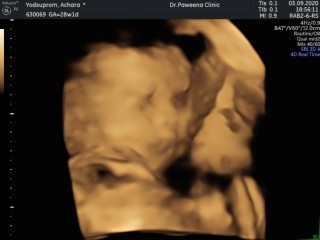

มาอวดรูปตอนซาวด์กันหน่อยค่ะ แม่ๆกำหนดคลอดเดือนไหนบ้างคะ